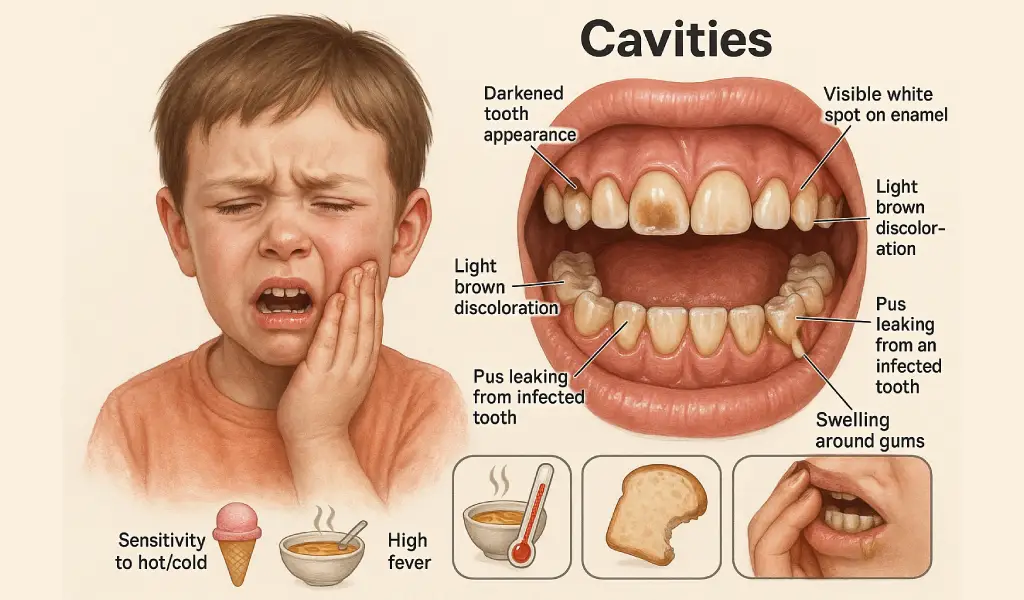

What are the Signs of Cavities in Kids?

There are various signs that a child is suffering from dental cavities. Kids’ cavities are visible from the following symptoms:

- Darkened tooth appearance

- Formation of white spots on teeth

- Light brown color on the tooth

- Holes or damage to the tooth

These are the basic visible signs of cavities in children. There’s another list of symptoms that signal that immediate dental attention is necessary:

- Excessive pain and swelling

- Difficulty chewing and sensitivity to hot and cold items

- High fever, indicating an infection

- Pus leaking out from the tooth